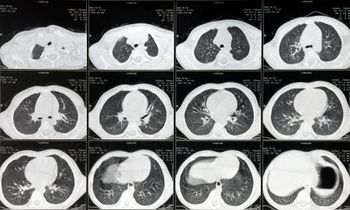

A retrospective analysis suggested that a declining proportion of patients with lung cancer would meet the criteria for undergoing low-dose CT screening.

This one-act play features a patient, former smoker, navigating the CMS rules for lung cancer CT screening in a shared decision-making session with his doctor.